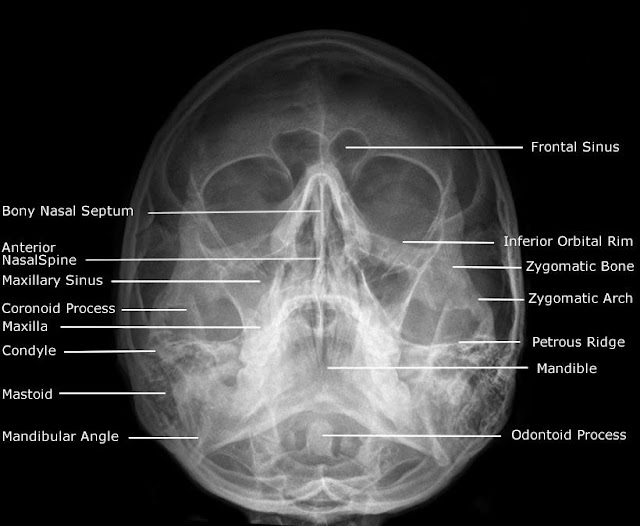

Radiographic Anatomy of Facial Bones and Mandible with Radiological Mandible X Ray Protocol Position the patient so that their back and posterior skull are touching the bucky. Patient is in an erect position, either standing or sitting. Mandible and maxilla oblique radiography. This projection is useful in identifying structural changes and displaced fractures of the mandible in a trauma setting, and in neoplastic or inflammatory changes. According to the anatomy of. A properly. Mandible X Ray Protocol.